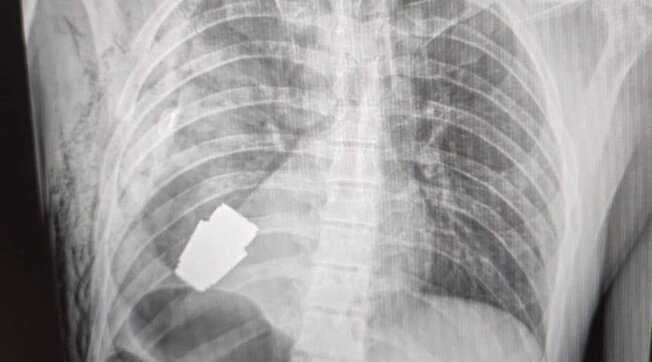

GRANATA-LASTRA

KYIV. Un soldato ucraino è stato operato con successo a Kyiv per la rimozione di una granata inesplosa dal petto, un intervento destinato a finire nei libri di testo di medicina. Il chirurgo ha estratto l’ordigno da appena sotto il cuore del militare. La vice ministra della Difesa ucraina, Hanna Maliar, in un post sui social ha mostrato la foto della radiografia che ritrae la granata all’interno del corpo del soldato e fa sapere che “i medici militari hanno effettuato un'operazione per rimuovere una granata Vog, che non è esplosa, dal corpo del soldato”, continua, “l’operazione è stata eseguita senza utilizzare l'elettrocoagulazione, un metodo comune per controllare il sanguinamento durante l'intervento chirurgico, perché la granata poteva esplodere in qualsiasi momento".

Anton Gerashchenko, consigliere ministeriale per gli affari interni dell’Ucraina, in un comunicato su Telegram dice che “la parte inesplosa della granata è stata prelevata da sotto il cuore. La granata non è saltata in aria, ma è rimasta esplosiva”.